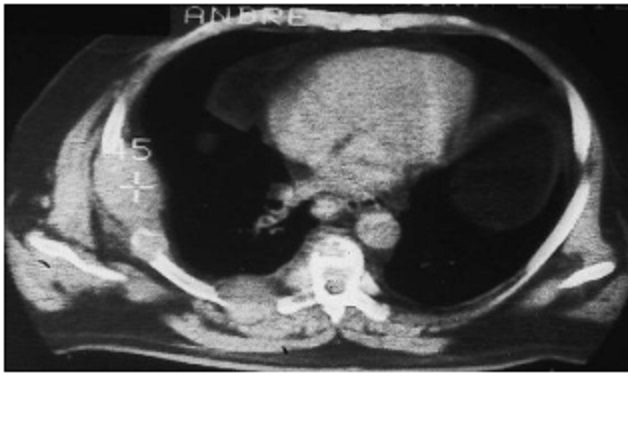

Syndrome pariétal avec lésion osseuse de hypodense

1/3 posterieure du cote droit (métastase

costale).

Image radiologique

TDM en coupe axiale |

Image radiologique TDM d'une tumeur

parietal à origine costale ( metastase costale ) |